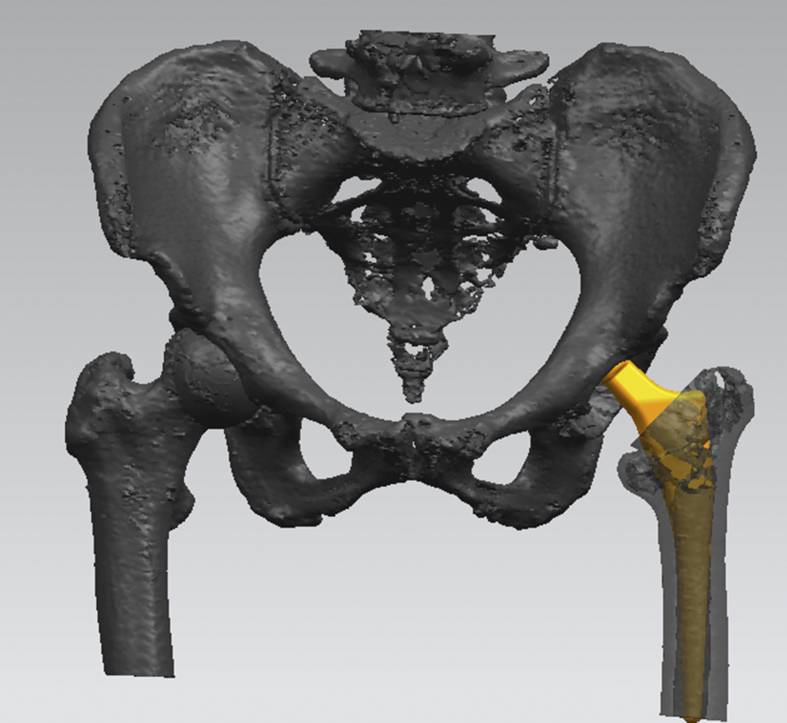

After admission, blood transfusion, intravenous iron supplement, erythropoietin subcutaneous injection and folic acid were offered to correct anemia, the HGB raised to 89 g/L, close to her basic level. We evaluated her basal metabolism by recording the intake and output volume. Hospital consultation was conducted preoperatively, and the related department collaboration and perioperative treatment plan were carefully made. Lumbar plexus, sciatic nerve and the lateral cutaneous nerve block were chosen. Perioperative intravenous infusion speed was controlled under 120 ml/h. And urine output remained at around 30 ml/h. The three dimensions visual template technology and hip fracture model printing ensured accurate measurement and evaluation (Fig. 2). After full preparation, she was offered the left artificial femoral head replacement with lateral position and posterolateral approach. We found that fracture line extended from the great trochanter to the top of the small trochanter with great trochanter avulsion fracture. The femoral neck was cut without dislocation. Then we took out the femoral head, reamed the cavity directly and inserted the implant mold. The fracture was stable, so we put the prosthesis to the fracture position apart from suturing of avulsion fracture (Fig. 3). The operation went smoothly and safely, with about 100 ml bleeding during the operation and 8 cm incision length.

Fig. 2.

The preoperative three dimensions visual template technology measured the size accurately.

Regarding surgical intervention, three dimensions visual template technology and hip fracture model printing ensured accurate measurement and evaluation, and hence reduced operative time. 3D printing model is conducive to doctor-patient communication and improves the surgical program.7 We used minimally invasive small incision, thorough hemostasis and shortened operation time as far as possible. Dislocation bone cutting technology could not avoid further enlargement of fracture wound. Through a rectangular conventional short shank prosthesis could achieve local stability, thus avoiding greater trauma and blood loss by the long handle prosthesis. A rectangular conventional short shank prosthesis could achieve local stability, which could avoid greater trauma and blood loss by the long handle prosthesis.